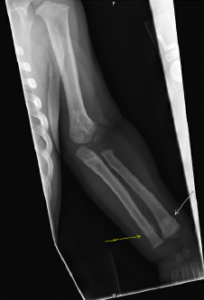

Figure 2 (LEFT): Radiograph of an arm fracture from a pediatric skeletal survey.